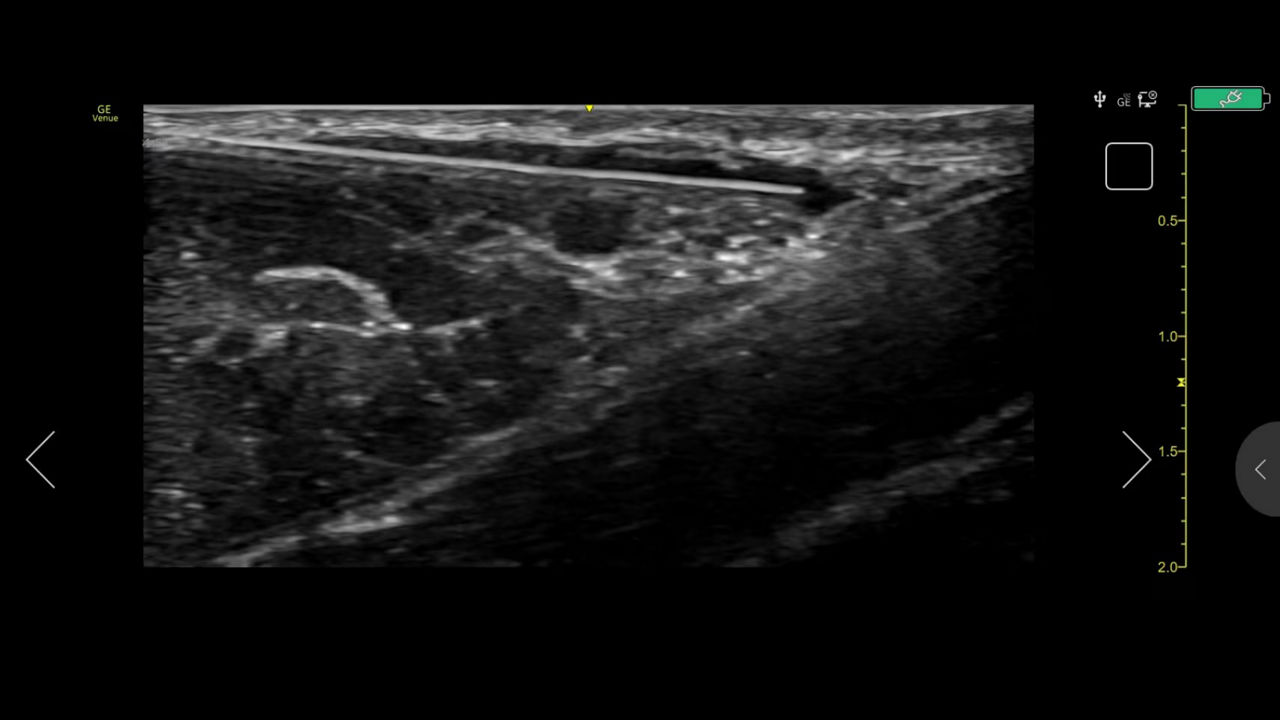

Precision Needle Guidance

Accurately guide and visualize injections

Even in the most experienced hands, blind injections—those performed without imaging—are not 100% accurate. By using ultrasound for needle guidance, the needle is highlighted and you have quality visualization of joints and soft tissue during procedures at a lower acquisition cost than other imaging modalities.

Excellent visualization with Needle Mode

Needle Mode also allows you to easily differentiate between the needle and patient anatomy with confidence—allowing you to quickly guide the needle exactly where it needs to be and helping to minimize patient discomfort.